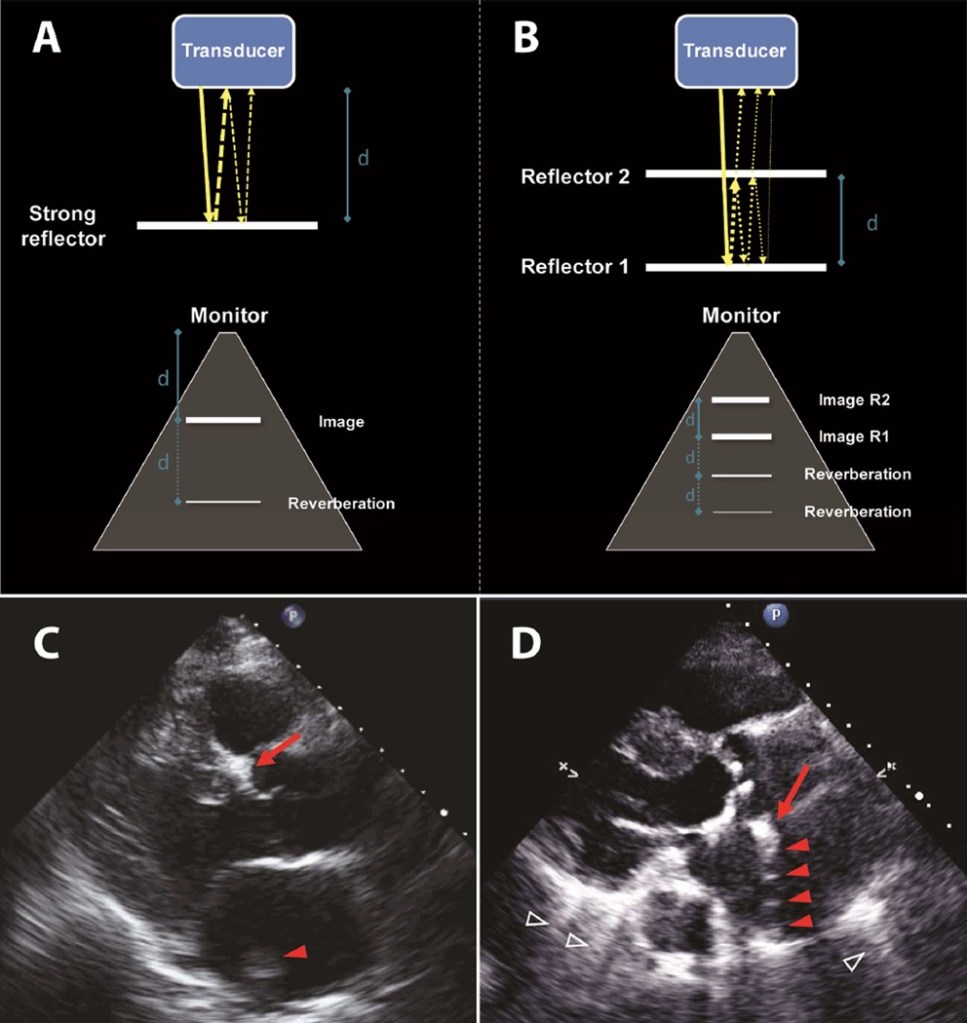

- Reverberations – happens between two strong parallel reflectors causing parallel dense lines extending from the structure into the the far field. It makes hard to evaluate structures in the far field because of that. “In the parasternal long axis view, a linear echo in the aortic root that originates as a reverberation from anterior structures like ribs may be mistakes for a dissection flap.” (Otto, Textbook of Clinical Echocardiography).